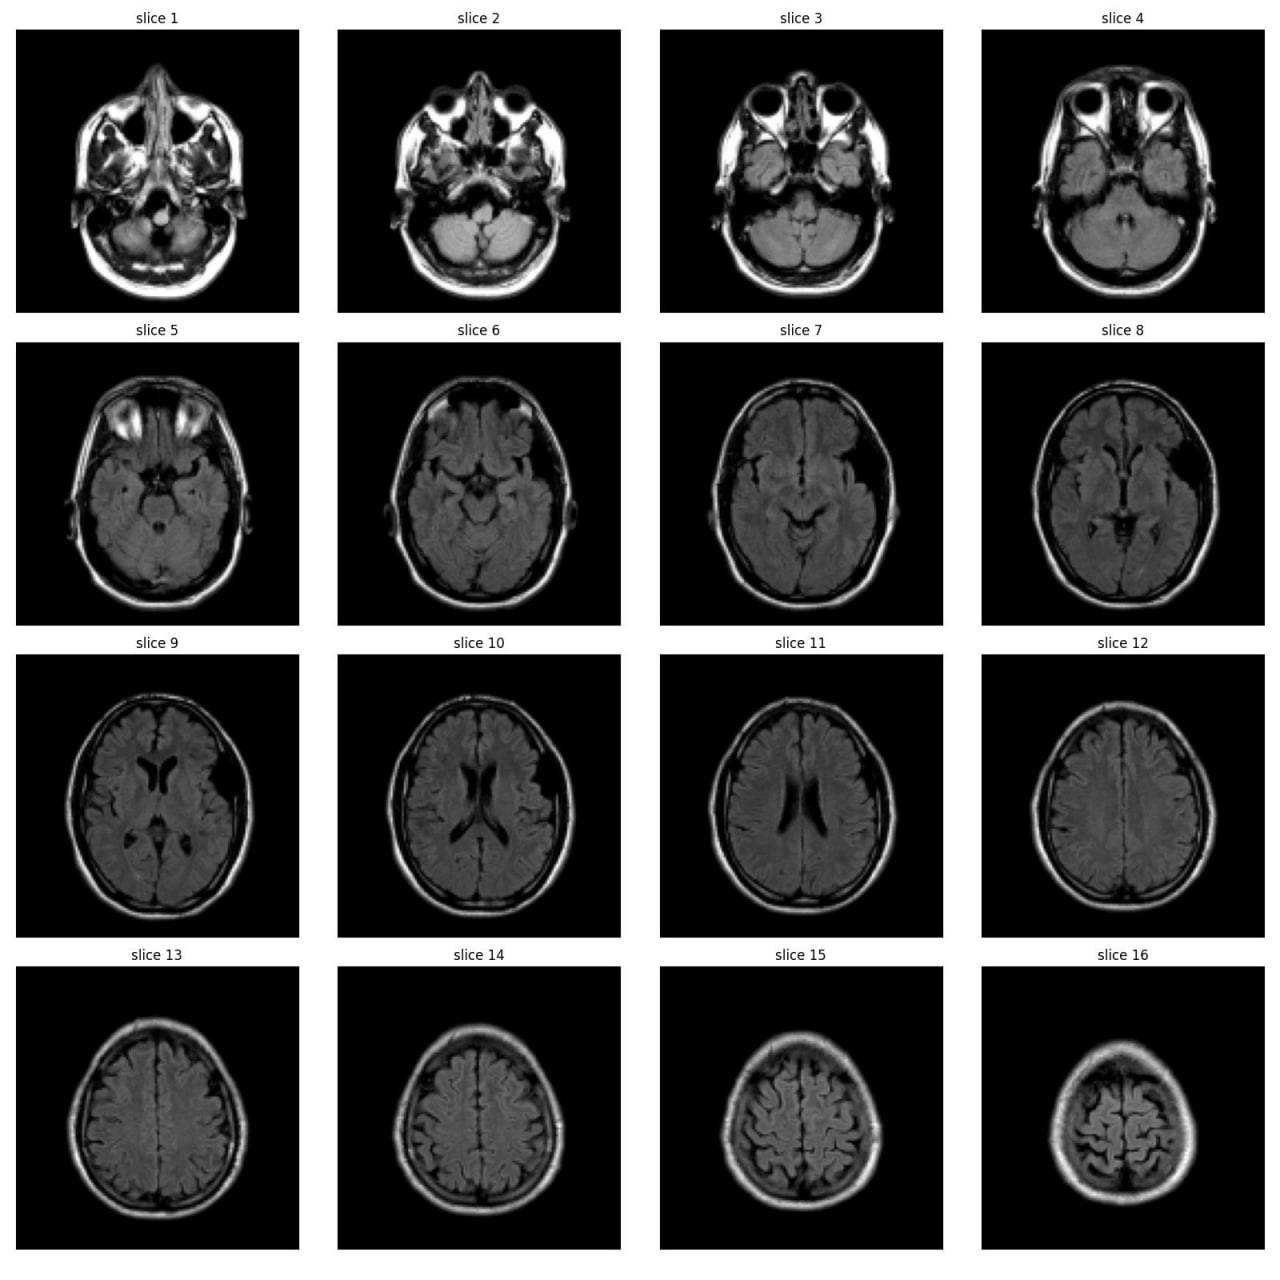

Abnormality Classification in Brain MRI

As part of the JIM3 team, I competed in the IAAA competition, which involved a dataset of 4,000 MRI images, with only 500 labeled as abnormal. The competition aimed to develop a model for patient-level abnormality classification. We utilized various models, including EfficientNet, DenseNet, ResNet, custom CNN models, and Vision Transformers (VIT), along with different preprocessing techniques. Working closely with a medical team, we converted subject-level annotations into slice-level annotations for more effective model training. Despite discovering inconsistencies in the test set and normal cases after the competition, we secured 17th place among over 100 teams. The technical team is currently working on a paper using the annotated data from this project.